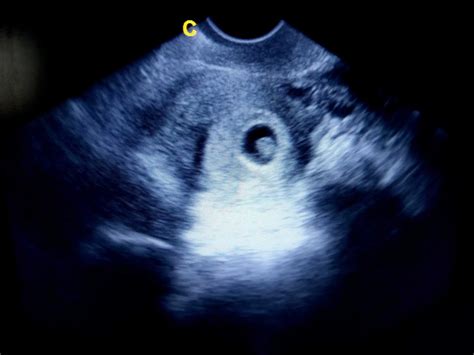

În săptămâna 5 de sarcină, acel nucleu de celule care s-a divizat constant se poate numi oficial embrion și are mărimea unei semințe de măr, aproximativ 1,25 mm, ceea ce este suficient pentru a putea fi observat la ecograf. Bebelușul sau embrionul are aproximativ 2 mm lungime în săptămâna 5 de sarcină, cam la fel de mare ca o sămânță de susan. Aceasta este perioada în care trăsăturile feței încep să prindă contur și se formează nasul și ochii, care rămân închiși până la aproximativ 28 de săptămâni (de dimensiuni foarte mici). Embrionul este vizibil (20 de zile), de mărimea unei gamalii de ac! El se dezvoltă de acum foarte repede, deși tu nu știi că ești însărcinată. Tot în săptămâna 5 de sarcină se formează și o placentă rudimentară și cordonul ombilical. Cu ajutorul acestora embrionul își primește atât oxigenul cât și nutrienții de la mamă. Un alt aspect important și, totodată, emoționant care apare în săptămâna 5 de sarcină este faptul că începe să-i bată inima. De fapt, acum este perioada în care se formează sistemul digestiv, sistemul circulator și sistemul nervos, primul fiind sistemul circulator. Inima este deocamdată formată din 2 mici canale, care vor fuziona și vor forma o inimă perfect funcțională. Din ziua 22 (săptămâna 6) după fertilizare, un test cu ultrasunete va putea detecta activitatea inimii copilului dumneavoastră. În acest stadiu, copilașul are inimă, inițial disproporțional de mare. Știați că în nicio etapă din timpul sarcinii, copilul nu primește oxigen prin plămâni? De fapt, singura modalitate prin care primește oxigenul de care are nevoie este prin placentă. Embrionul începe să se dezvolte foarte repede, deși tu nu știi că ești însărcinată. Placenta se dezvoltă în continuare. În săptămâna a 5-a începe dezvoltarea sistemului nervos central și a oaselor. Tot acum se formează fața, ochii, gura și nasul și se conturează tălpile. Forme de mânuțe și degete rudimentare se dezvoltă. Fătul trece prin schimbări semnificative: la sfârșitul celei de-a cincea săptămâni de sarcină va arăta ca un mormoloc și va avea inclusiv coadă. De asemenea, organele vitale, precum inima, sistemul nervos central, oasele și mușchii încep să se dezvolte, la fel și tubul neural. Nu îți dai seama, dar creierul bebelușului tău se dezvoltă rapid prin apariția celor două emisfere cerebrale, cele două părți ce vor alcătui creierul său. Organele de simț apar și ele, prin conturarea ochilor și a urechilor și prin debutul nasului și a gurii. De asemenea, fața începe să prindă contur. În mod fascinant, sistemul său pulmonar și cel digestiv prind formă puțin câte puțin. Inima bebelușului tău s-a dezvoltat suficient încât să devină mai proeminentă - o ecografie în această etapă va arăta cu siguranță bătăile inimii lui! Copilul crește într-un ritm tot mai accelerat, iar de la embrionul de mărimea unei afine, în săptămâna 8 de sarcină el ajunge deja la mărimea unei zmeure. Copilul are mărimea unei afine în săptămâna 7 de sarcină. Practic, dimensiunea embrionului este de zece mii de ori mai mare decât era în urmă cu o lună. Săptămâna 6 de sarcină este perioada în care embrionul este curbat și are formată o prelungire ce seamănă cu o coadă, arătând ca un mormoloc de dimensiuni mici. Desi este doar cât un bob de mazăre, bebelușul tău crește cu repeziciune. Nu asculta poveștile despre naștere ale oricui, te pot impresiona negativ. Lanugo și stratul de vernix care acoperă pielea încep să dispară, greutatea lui este de 2400 grame, poți deja să faci planuri de naștere cu familia. Se pot repeta acum analizele pentru a verifica absența anemiei și eventual anticorpii în incompatibilitate de grup sau de Rh. Pot apărea contracții uterine ușoare, care pregătesc fibra musculară pentru travaliu, dar nu fac modificări de col (Braxton - Hicks). Acum fătul are aspect de bebeluș, cresc și unghiile de la picioare; membrele sunt flectate și are mai puțin spațiu să se miște. Poti să-ți faci de pe acum bagajul pentru spital.